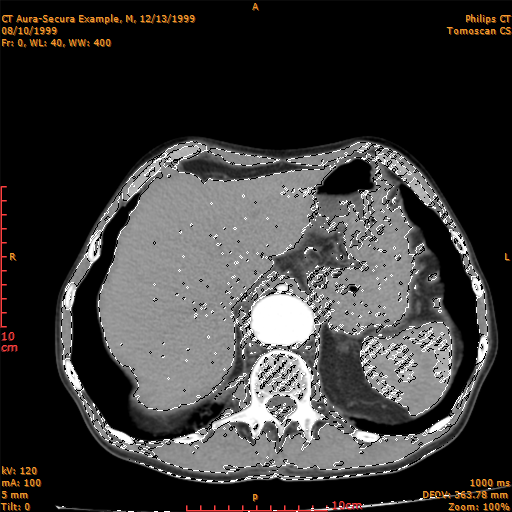

Modify a selection: Inverse Selection

Use the command SelectionModifyInvert to invert a selection to select the opposite part of the image. This command selects all the unselected areas and deselects any selected one, thus inverts the selection.